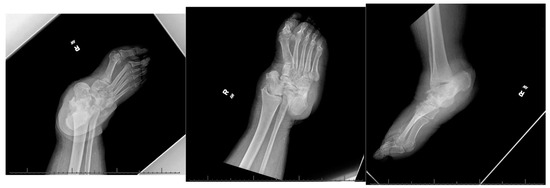

A 66-year-old morbidly obese African American female with a past medical history significant for congestive heart failure (CHF), uncontrolled type 2 diabetes mellitus (DM) with peripheral neuropathy, chronic stage 4 kidney disease (CKD), hyperlipidemia, hypertension (HTN), gastroesophageal reflux disease (GERD), obstructive sleep apnea (OSA), multiple joint arthritis, depression, and asthma, among other diagnoses, had presented to the emergency room with right foot pain and swelling for about two weeks. She was diagnosed with cellulitis of the foot and was sent to medicine service for management. The plain radiographs (Figure 1) showed talonavicular dislocation and marked degenerative changes consistent with Charcot arthropathy. She received intravenous (IV) antibiotics for three days and was discharged on oral antibiotics with instructions to follow up in orthopedic clinic. She returned to the emergency department two weeks later with fever and worsening symptoms of foot pain, accompanied by a draining medial hindfoot ulcer.

Figure 1. Preoperative radiographic images.